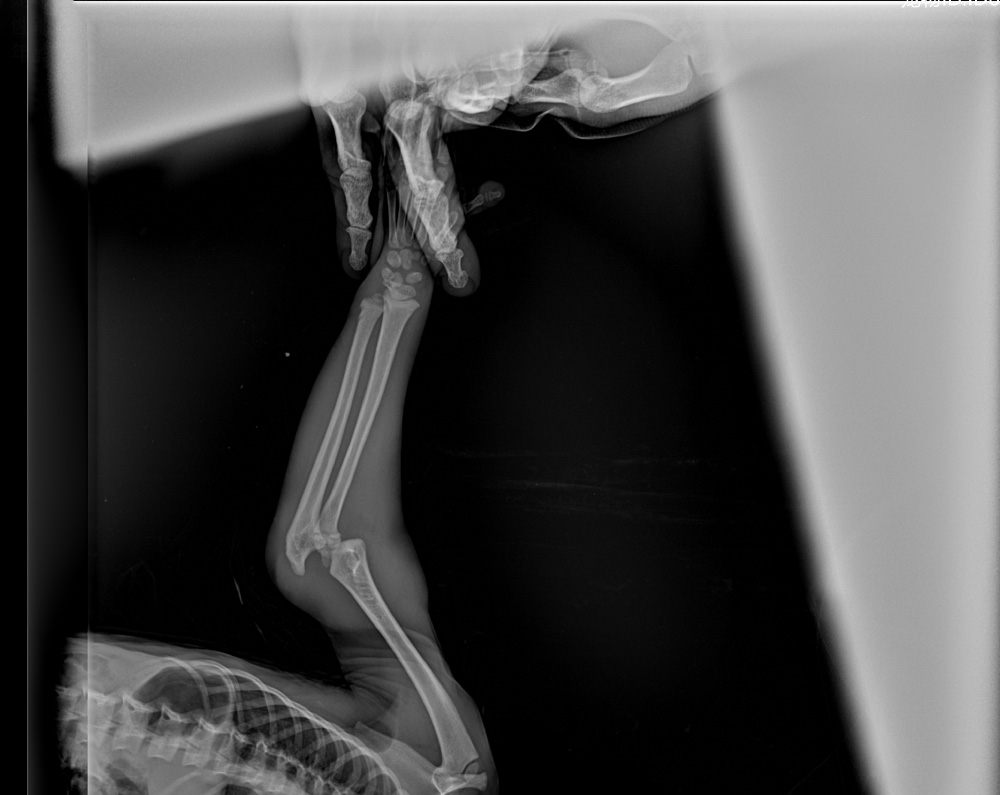

我们始终将动物的健康管理置于首位。通过健康检查、疫苗接种、寄生虫筛查、驱虫治疗及新引进动物隔离检疫等措施,构建完善的预防医学体系。当动物出现健康问题时,兽医团队会及时开展诊治,并根据需要邀请外科、牙科、眼科、骨科等专家参与会诊,确保各类复杂病症得到专业处理。